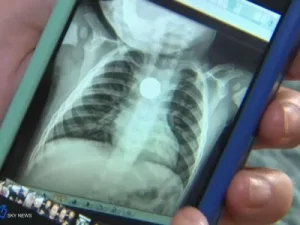

وتم استخراج العظمة من المنصف الصدري خلف القلب مباشرة، بالقرب من القصبة الهوائية، بعد أن ثقبت المريء، ذلك من خلال ترقيع المريء وتنظيف المنطقة قرب القلب من التعفن الذي سببه العظم، بعد استقراره في المنطقة لمدة 3 أيام”.

الطبيب العراقي كشف أن “هذه العملية عالية الخطورة، إذ تصل نسبة الوفاة فيها إلى 45%”، موضحاَ أن “بقاء الجسم الغريب لأكثر من يوم بالمنصف الصدري يسبب التهابا بكتيريا بالأنسجة القريبة من القلب، وتسمما بالدم.”.